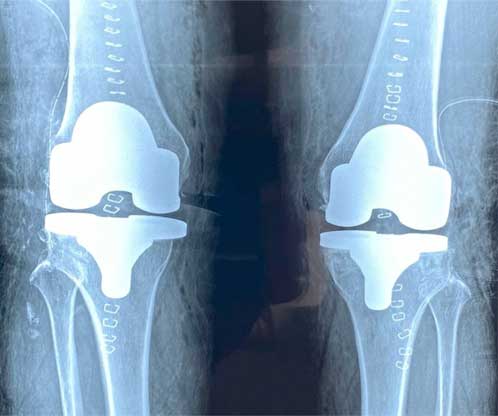

Prótesis de rodilla

También conocida como artroplastia de rodilla, es la sustitución artificial de la articulación desgastada por artrosis con un implante de metal y polietileno que ayuda a aliviar el dolor y restaurar la función.

¿Por qué se realiza?

La razón más frecuente es aliviar el dolor intenso causado por artrosis, corregir las deformidades angulares en varo, valgo y contractura en flexión en adultos mayores y para adultos jóvenes, está indicada en lesiones crónicas articulares que ocasionan un desgaste acelerado.

Cuidados después de la intervención

El paciente puede caminar desde el mismo día de la cirugía, se da de alta a su domicilio a las 24 horas, realiza actividades cotidianas en casa de forma autónoma desde la primera semana, recupera el 80% de la función de la rodilla al primer mes, 90% de la función en el segundo mes y 92% - 98% de la función en el tercer mes.

Resultados esperados

Eliminar el dolor en la zona afectada, mejorar la función como es fuerza muscular, movimiento, estabilidad, biomecánica, logrando mejorar la calidad de vida del paciente.